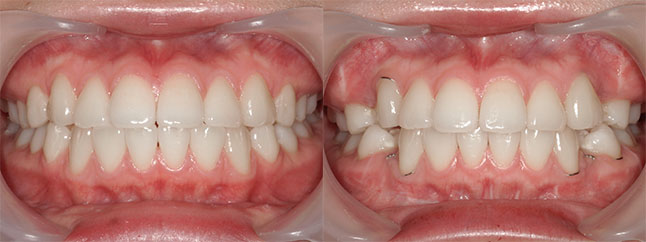

奈良県 20歳 女性

執刀医 辻和志

【治療内容】上下のアゴが前に出ていたため、上下のアゴの骨を切って後ろにさげました。

【費用】上下セットバック 2,307,800円(税込)

【リスク】全身麻酔で行うため全身の健康状態が悪い方は行うことができません。また、手術当日は安静にしていただく必要があります。